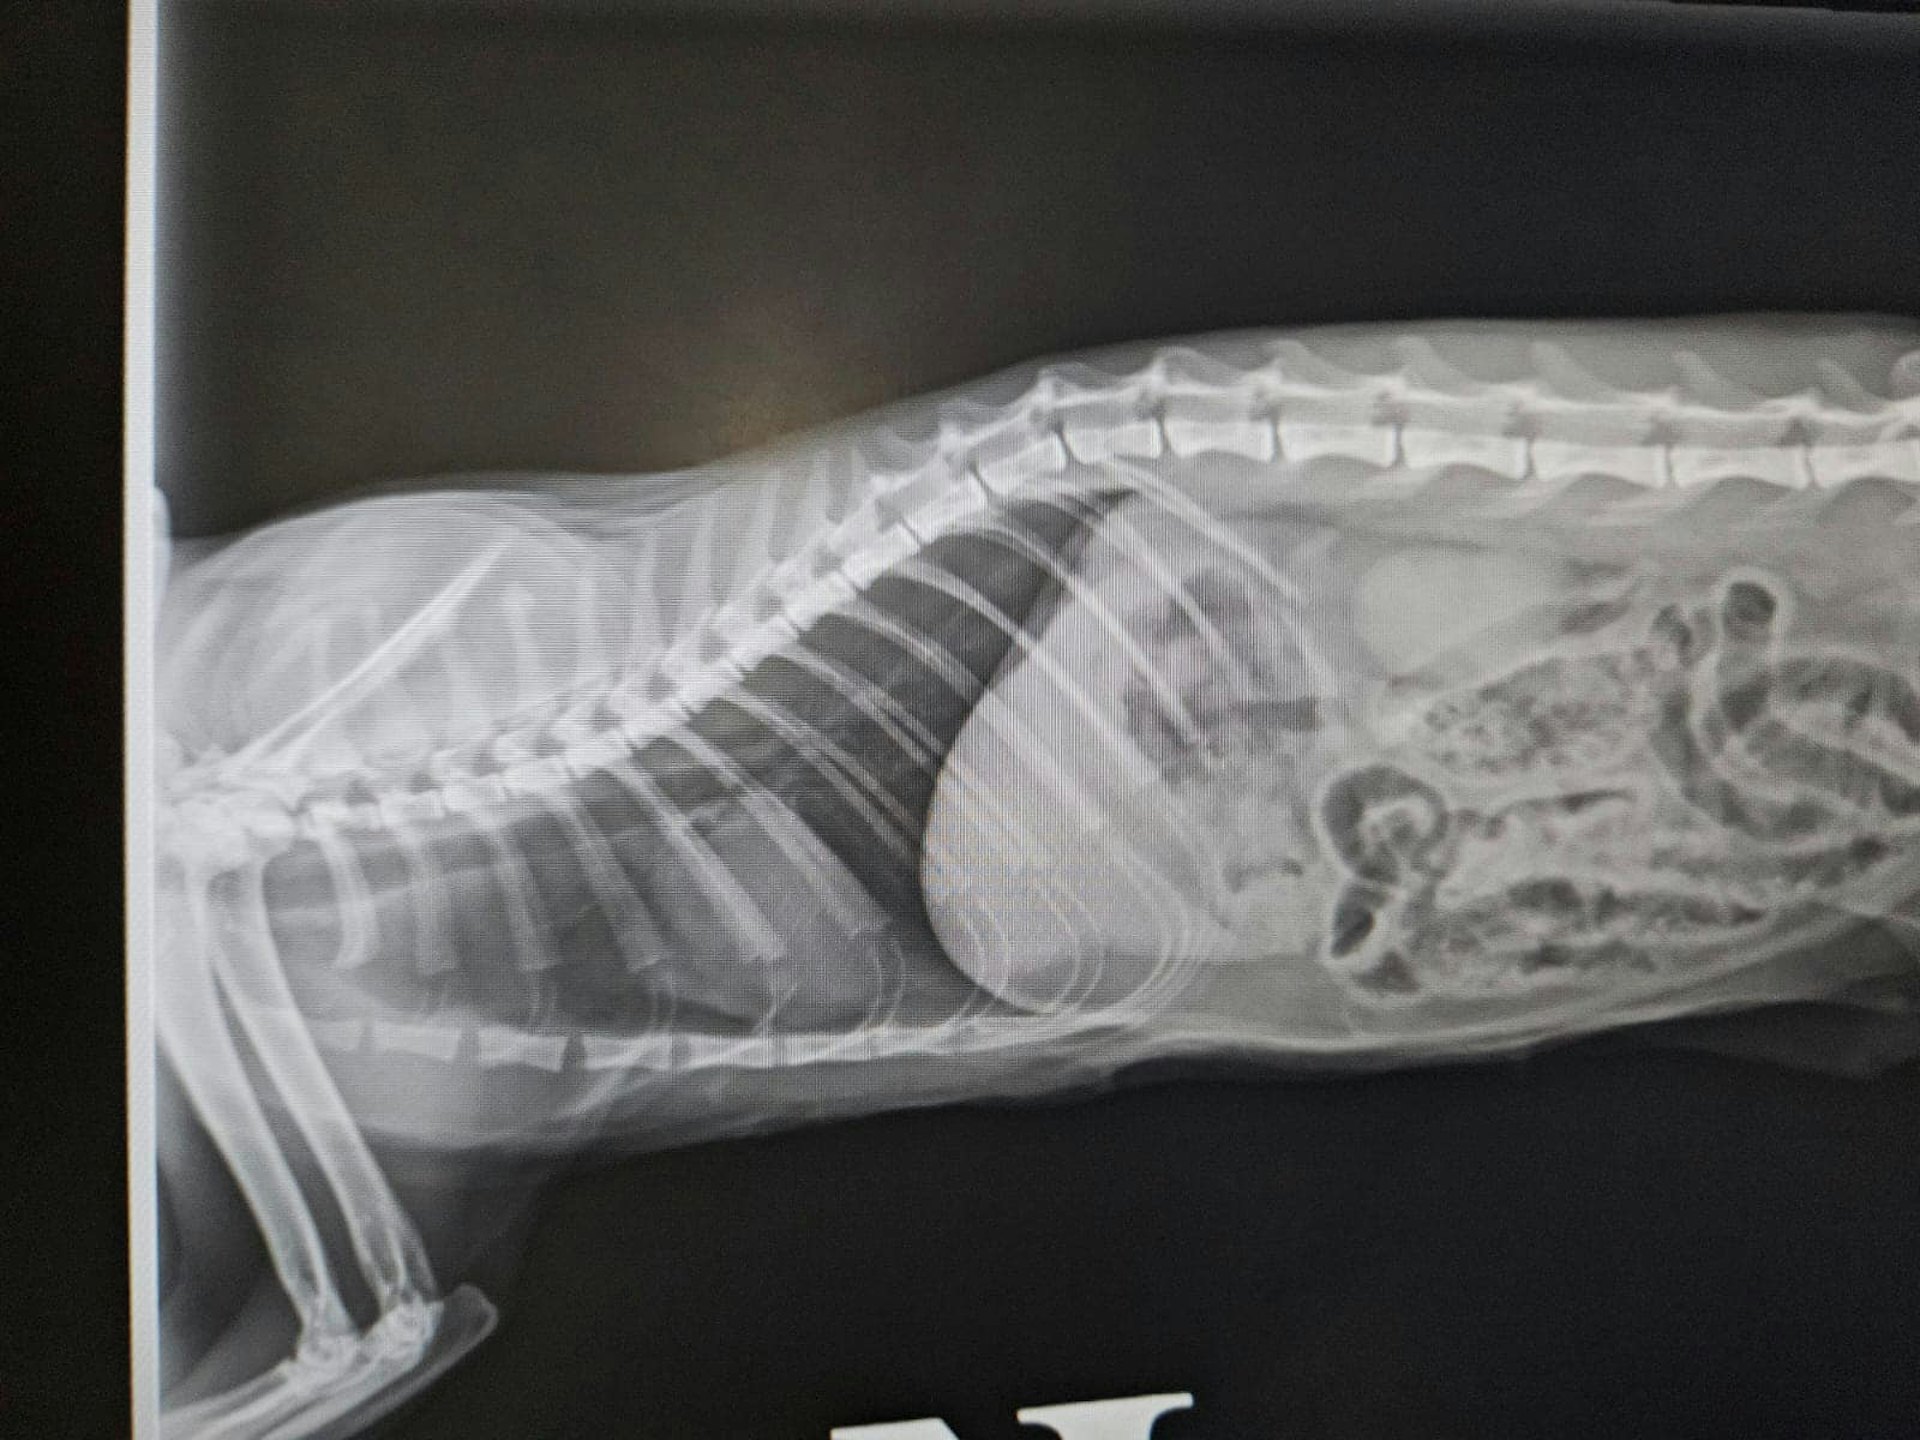

受傷貓隻接受X光檢查。(facebook專頁「毛守救援」圖片)